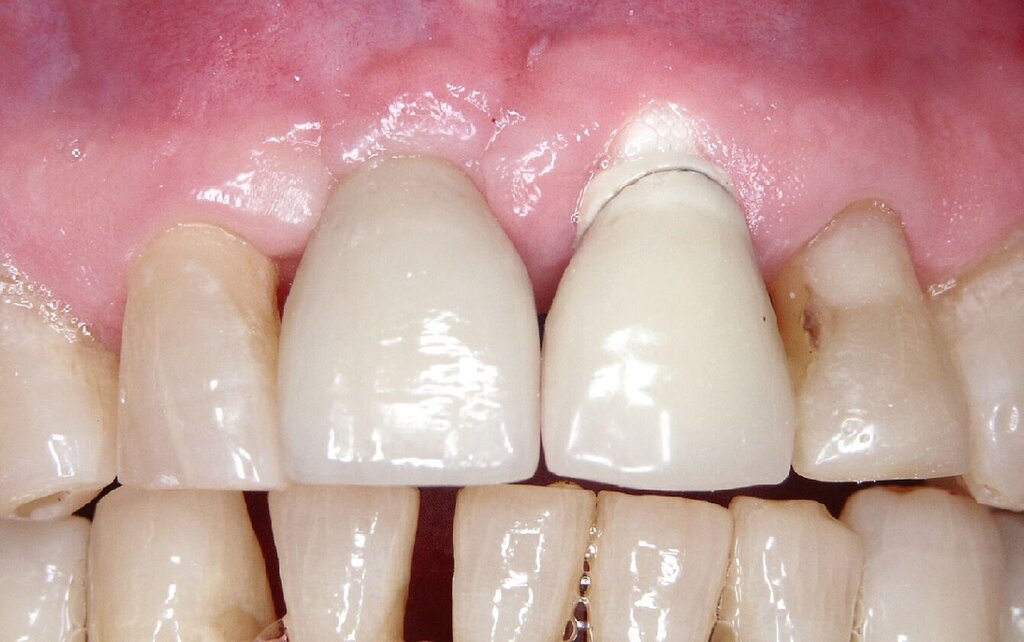

Bei einem 76-jährigen Patienten wurde ein circa 20 Jahre altes Aluminiumoxid-Implantat (Abb. 2a) entfernt, nachdem die ausgeprägte Gingivarezession in Kombination mit dem Abbau der vestibulären Knochenlamelle keine ausreichende Mundhygiene mehr zuließ. Nach Entfernung der Krone auf dem intakten Implantat in regio 11 konnte zur provisorischen Lückenversorgung eine stuhlgefertigte, kombiniert Zahn/Implantat-gestützte Brücke von 011 auf 22 eingegliedert werden (Abb. 2b). Eine Nachimplantation war aufgrund der günstigen Prognose für den Pfeilerzahn 22 überflüssig. Das verbliebene Weichgewebsdefizit wurde drei Monate nach der Explantation mit einem Bindegewebstransplantat vom harten Gaumen kompensiert (Abb. 2c bis 2e). Nach einer Konsolidierungsphase von weiteren drei Monaten wurde das Provisorium durch eine monolithische Zirkoniumdioxidbrücke mit ausschließlich vestibulärer Verblendung ersetzt (Abb. 2g). Eine invasive knöcherne Augmentation mit Wiederherstellung des knöchernen Kieferkamms nach dem Implantatverlust in regio 21 konnte vermieden werden, da eine erneute Implantation für das Behandlungsziel einer festsitzenden Versorgung nicht nötig war.